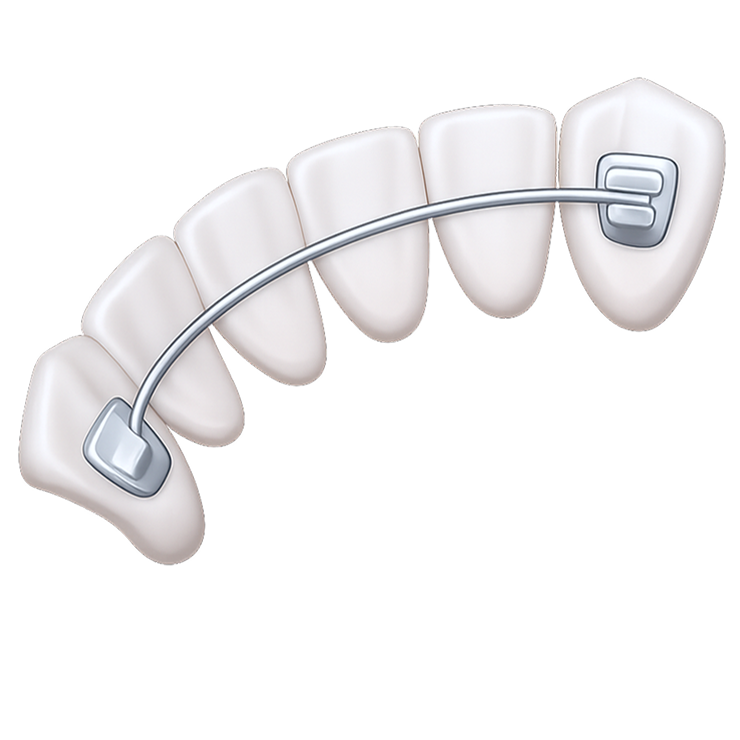

Замена всех зубов на импланты

На место каждого отсутствующего зуба устанавливается имплантат, а на него – отдельная коронка. После того, как импланты приживутся, они ничем не будут уступать собственным.

Установка имплантов вместо всех зубов предотвращает атрофию челюстной кости. Имплантат выполняет роль зубного корня и передает на челюстную кость жевательную нагрузку, аналогичную той, которую она испытывает при наличии собственных зубов. Не заметит разницы и сам пациент.